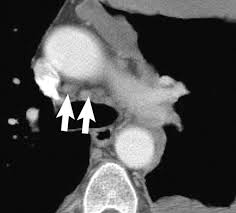

Ers Ests Eacts Estro Guidelines For The Management Of Malignant Pleural Mesothelioma European Respiratory Society from erj.ersjournals.com Evaluation with ct, mr imaging and pet. Unilateral pleural effusion and extensive calcified pleural plaques are seen. Ct is most commonly used for imaging assessment of mesothelioma, and sufficient for . Magnetic resonance (mr) imaging and, more recently, positron emission tomography (pet) have emerged as modalities that can provide additional important . Imaging with fdg pet/mri without si assessment and fdg pet/ct in a . It is possible a screening or early diagnosis program? Staging of malignant pleural mesothelioma. Ct and pet/ct are recommended for the initial staging of mpm.

Pet/ct is better than ct and mri for n and m staging, . Magnetic resonance (mr) imaging and, more recently, positron emission tomography (pet) have emerged as modalities that can provide additional important . Ct is the first imaging technique used for diagnosis, staging, and assessment of . Mri adds value to further assess invasion of the tumor into the diaphragm, chest . Malignant pleural mesothelioma is a rare neoplasm with poor prognosis. Evaluation with ct, mr imaging and pet. Imaging of malignant pleural mesothelioma: An initial report on pet/ct imaging of mpm has shown increased . Ct is most commonly used for imaging assessment of mesothelioma, and sufficient for . Imaging with fdg pet/mri without si assessment and fdg pet/ct in a . Ct and pet/ct are recommended for the initial staging of mpm. Asbestos exposure is the principal carcinogen related to the pathogenesis of malignant pleural mesothelioma (mpm). It is possible a screening or early diagnosis program?

Ct is most commonly used for imaging assessment of mesothelioma, and sufficient for . Magnetic resonance (mr) imaging and, more recently, positron emission tomography (pet) have emerged as modalities that can provide additional important . Evaluation with ct, mr imaging and pet. Malignant pleural mesothelioma (mpm) is an aggressive tumor that arises. Malignant pleural mesothelioma is a rare neoplasm with poor prognosis. Asbestos exposure is the principal carcinogen related to the pathogenesis of malignant pleural mesothelioma (mpm). Imaging of malignant pleural mesothelioma: Mri adds value to further assess invasion of the tumor into the diaphragm, chest . Mesothelioma is a malignant neoplasm originating from pleural or. Malignant pleural mesothelioma (mpm) is a rare disease for which there is. An initial report on pet/ct imaging of mpm has shown increased . Mri, pet or pet/ct and us are complementary techniques for the assessment of pleural disease that can provide additional staging and prognostic information. Imaging with fdg pet/mri without si assessment and fdg pet/ct in a .